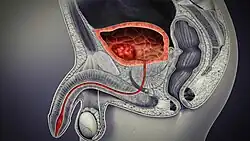

Cancer

Cancer of the bladder is known as bladder cancer. It is usually due to cancer of the urothelium, the cells that line the surface of the bladder. Bladder cancer is more common after the age of 40, and more common in men than women;[33] other risk factors include smoking and exposure to dyes such as aromatic amines and aldehydes.[33] When cancer is present, the most common symptom in an affected person is blood in the urine; a physical medical examination may be otherwise normal, except in late disease.[33] Bladder cancer is most often due to cancer of the cells lining the ureter, called transitional cell carcinoma, although it can more rarely occur as a squamous cell carcinoma if the type of cells lining the urethra have changed due to chronic inflammation, such as due to stones or schistosomiasis.[33]

Investigations performed usually include collecting a sample of urine for an inspection for malignant cells under a microscope, called cytology, as well as medical imaging by a CT urogram or ultrasound.[33] If a concerning lesion is seen, a flexible camera may be inserted into the bladder, called cystoscopy, in order to view the lesion and take a biopsy, and a CT scan will be performed of other body parts (a CT scan of the chest, abdomen and pelvis) to look for additional metastatic lesions.[33]

Treatment depends on the cancer's stage. Cancer present only in the bladder may be removed surgically via cystoscopy; an injection of the chemotherapeutic mitomycin C may be performed at the same time.[33] Cancers that are high grade may be treated with an injection of the BCG vaccine into the bladder wall, and may require surgical removal if it does not resolve.[33] Cancer that is invading through the bladder wall may be managed by complete surgical removal of the bladder (radical cystectomy), with the ureters diverted into a segment of part of ileum connected to a stoma bag on the skin.[33] Prognosis can vary markedly depending on the cancer's stage and grade, with a better prognosis associated with tumours found only in the bladder, that are low grade, that do not invade through the bladder wall, and that is papillary in visual appearance.[33]